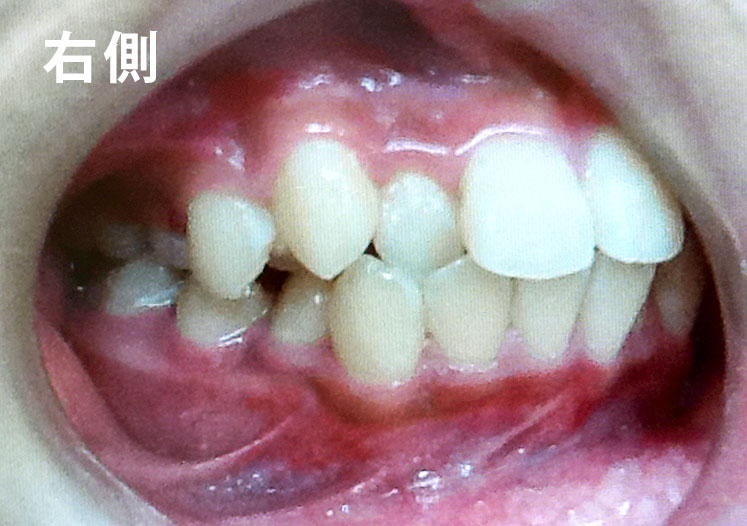

矯正bofore

矯正種類 ワイヤー矯正

症例 上下額叢生

治療期間 2021年12月〜2024年10月

性別/年代 男 13歳

治療費 748,000円

適切な時期に治療が開始できたので、歯並びだけでなく顎や顔貌も理想的に成長しました。歯磨きもしっかりできるようになりました。